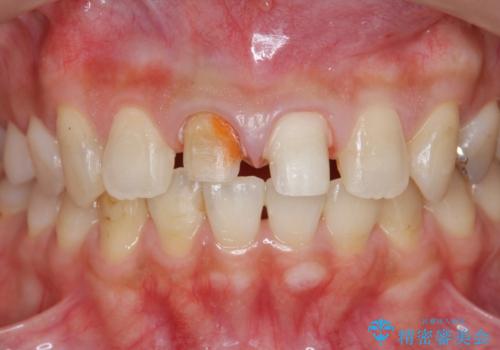

- 「 以前神経を取った歯の変色が気になる。前歯をきれいにして欲しい。」と治療を希望され来院されました。

目立つ上顎前歯に変色・大きな虫歯治療痕が見られ、審美障害を引き起こしています。